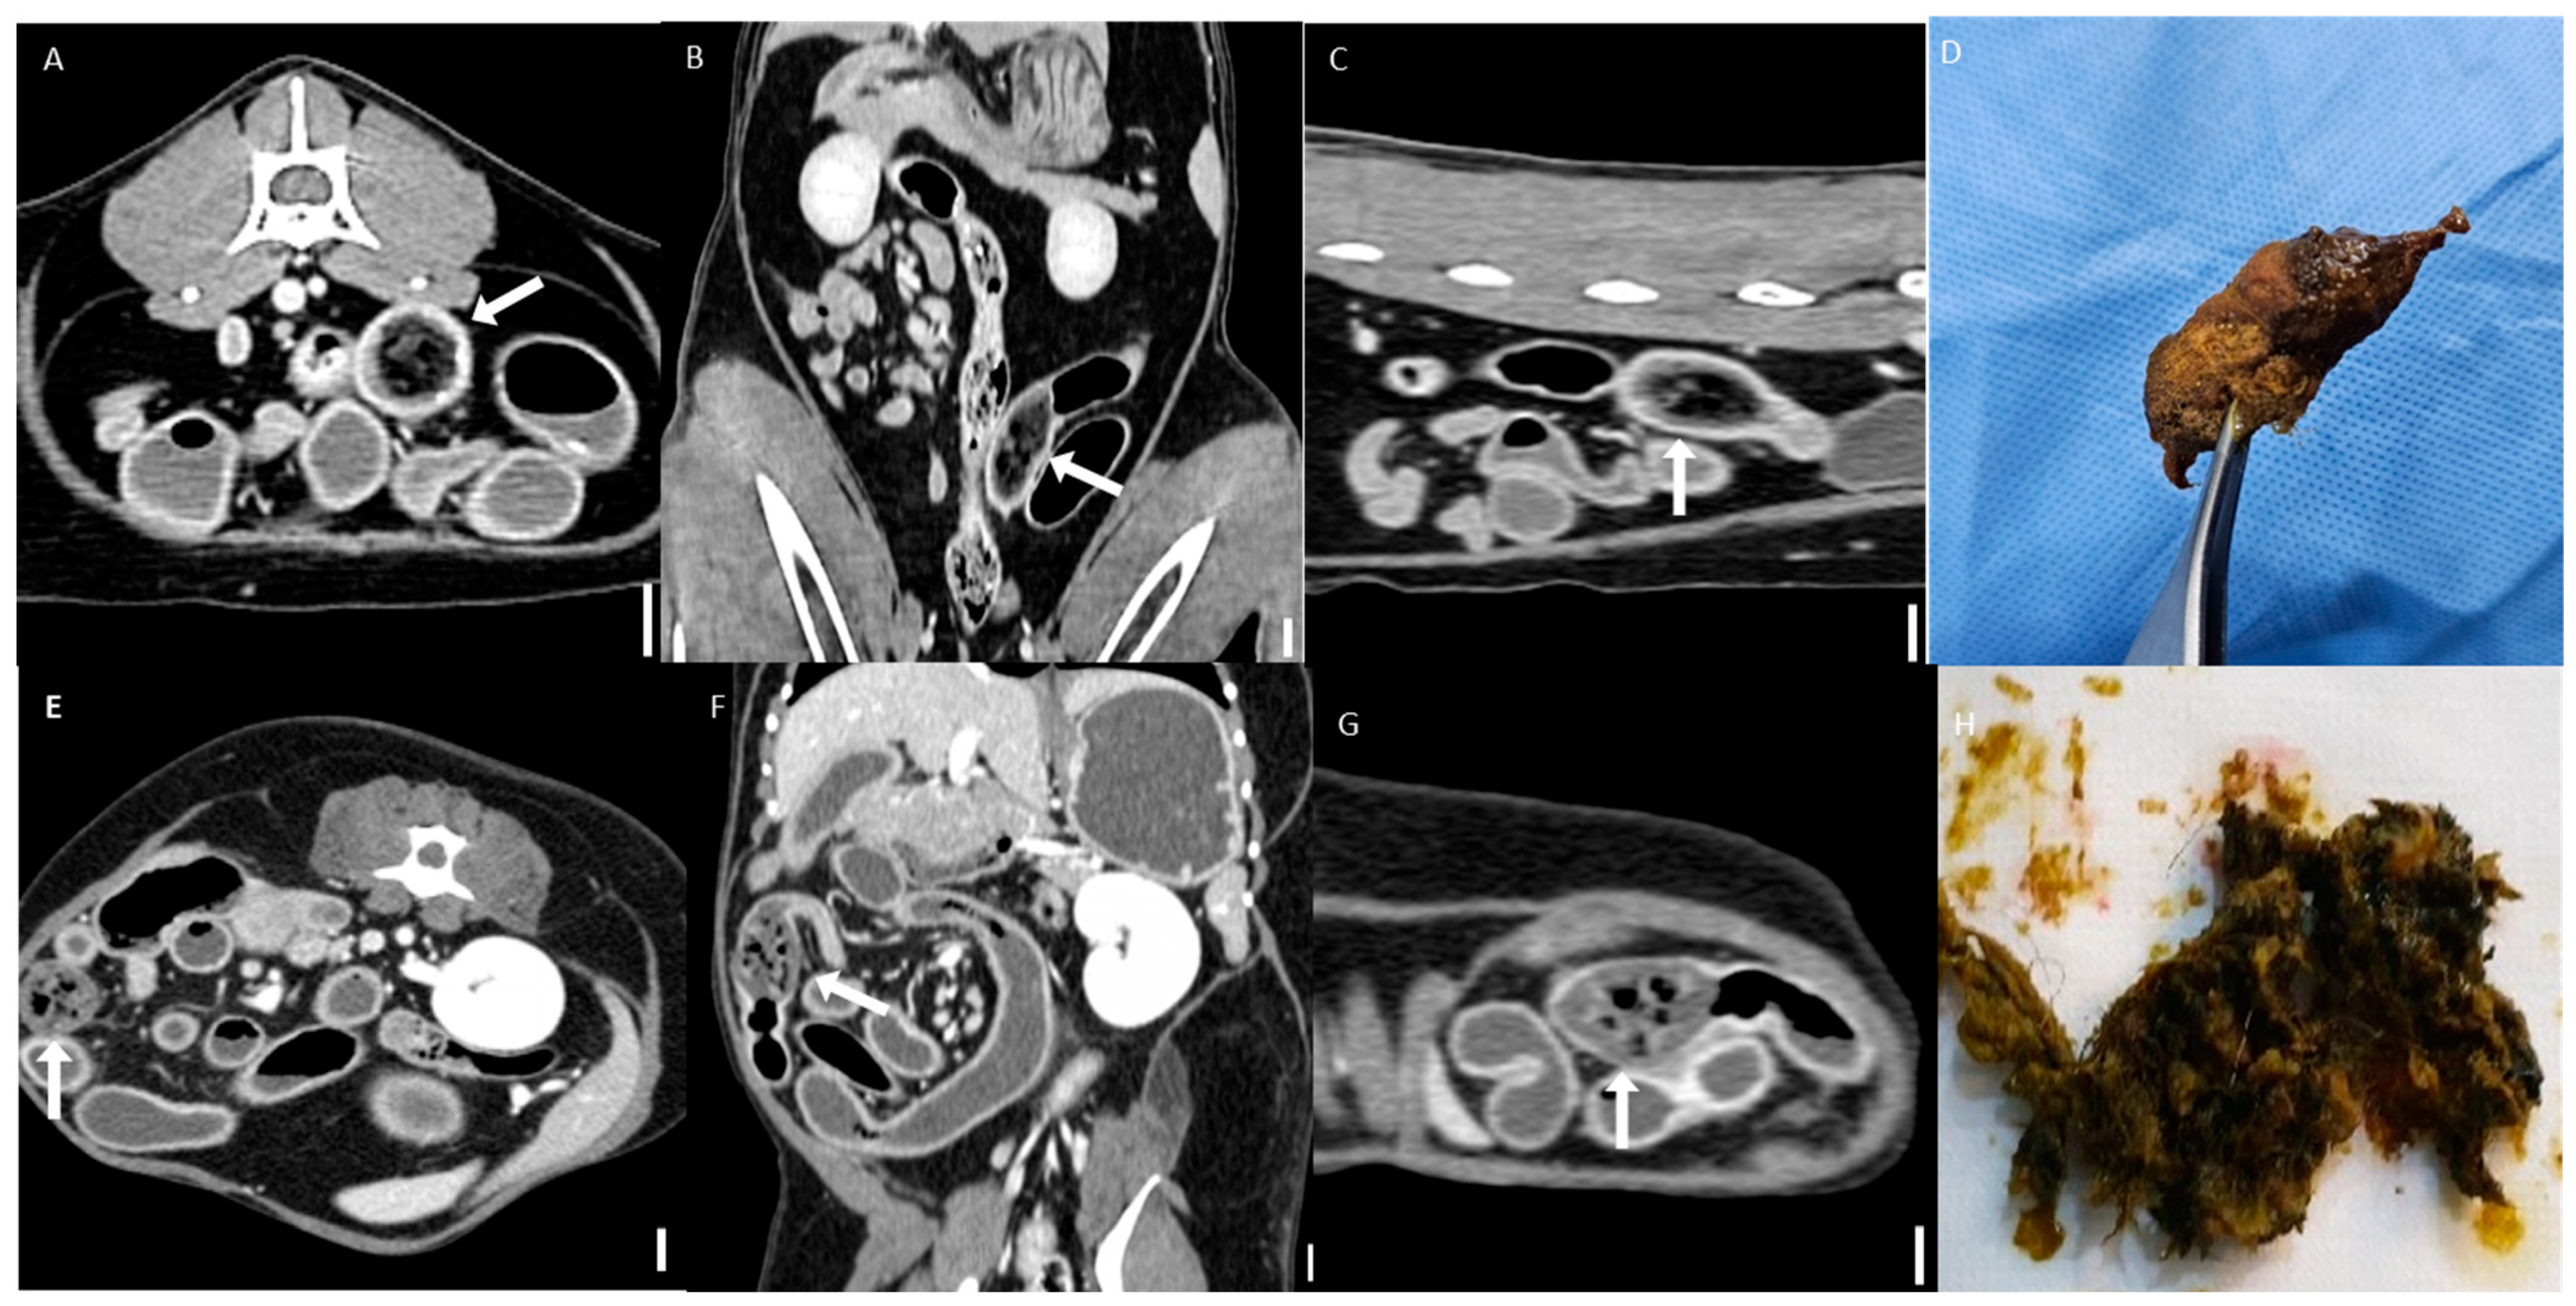

Figure 5. Representative CT images of bezoars (scale bar equals 1 cm). (AC) Multiplanar CT images of a jejunal bezoar: (A) transverse, (B) dorsal, and (C) sagittal views. The bezoar (arrows) appears as an intraluminal mass with a mottled gas pattern. (D) The corresponding surgically removed bezoar was identified as a trichobezoar composed of hair. (EG) Multiplanar CT images of another jejunal bezoar: (E) transverse, (F) dorsal, and (G) sagittal views. The bezoar (arrows) exhibits similar mottled gas appearance. (H) The corresponding foreign body was identified as a trichobezoar primarily composed of synthetic fibers, likely originating from toy fragments.

All bezoars were mostly classified into the suspected group based on CT imaging and displayed heterogeneous attenuation. They typically appeared as intraluminal masses with a mottled gas pattern, characteristic of their heterogeneous internal structure (Figure 5). Two cases—one in the trichobezoar group and one in the foreign body bezoar group—were visible on CT imaging and exhibited distinct boundaries. A comprehensive analysis of specific HU values is presented in Section 3.5.